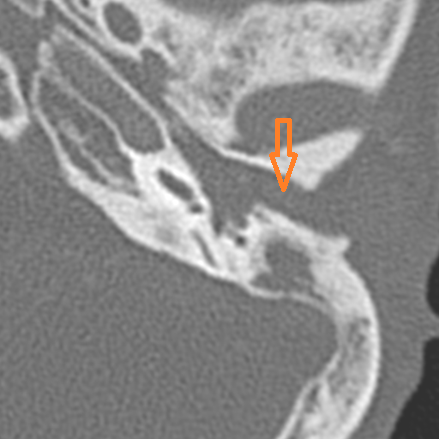

The ossicles; in particular the incus long process, the incudostapedial joint and stapes are eroded or displaced.

The facial canal and nerve are abnormal.